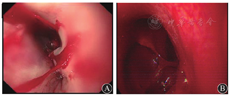

患者男,40岁,既往有糖尿病史,血糖控制不佳,否认肿瘤家族史,否认吞咽异物病史。此次因"消瘦10年,胸骨后疼痛、发热3 d"于2015年8月3日由急诊收治入院。临床表现为无明显诱因出现发热,体温最高达39 ℃,伴畏寒,无寒战,伴胸骨后疼痛,伴反酸、胃灼热、嗳气,且逐渐出现吞咽疼痛,遂入院治疗。入院体格检查:体温为37.4 ℃,脉搏为77次/min,呼吸为20次/min,血压为125/87 mmHg(1 mmHg=0.133 kPa);皮肤、巩膜无黄染,胸骨后无压痛,双肺呼吸音粗,未闻及干湿啰音,腹软,无压痛、反跳痛,双下肢不肿。入院诊断:2型糖尿病,反流性食管炎,咽炎,发热待查。给予抗炎、抑酸、保护胃黏膜治疗。入院后患者体温逐渐升高,出现呃逆,呕鲜血,胸骨后刀割样疼痛。实验室检查白细胞计数较前明显升高。8月5日行胸部CT平扫检查示:双侧胸膜增厚,双侧胸腔积液,食管旁憩室?食管扩张并管壁增厚。胃镜检查(图1)示:距门齿25 cm处食管3点位可见直径约0.5 cm的圆形孔道,较深,底部观察不清,胃腔内可见血液,考虑食管憩室、反流性食管炎、上消化道出血。给予加强抗炎、抑酸、止血、维持内环境稳定治疗。患者仍诉间断胸痛,8月6日复查胃镜(图2)过程中突发间断呕鲜血共约1 200 mL,出现低血压休克,迅速给予相关治疗维持生命体征。生命体征平稳后完善胸部CT增强检查(图3)示:主动脉弓局限性高密度灶,考虑主动脉假性动脉瘤可能?中上隔增宽,结构紊乱,多发积气,感染可能;食管中上段结构显示欠清,食管管壁不均匀增厚;纵隔内、左侧腋窝多发肿大淋巴结;胃腔内较多内容物;双下肺炎,双侧胸腔积液、心包积液。结合患者病史、影像学检查,考虑该患者可能为上消化道出血、主动脉瘘并出血、食管憩室炎、纵隔感染、类白血病反应、肺炎、胸腔积液、2型糖尿病。向家属说明病情建议行外科手术治疗。但患者突然出现血压下降,心肺复苏未成功,于8月6日18:00时临床死亡。